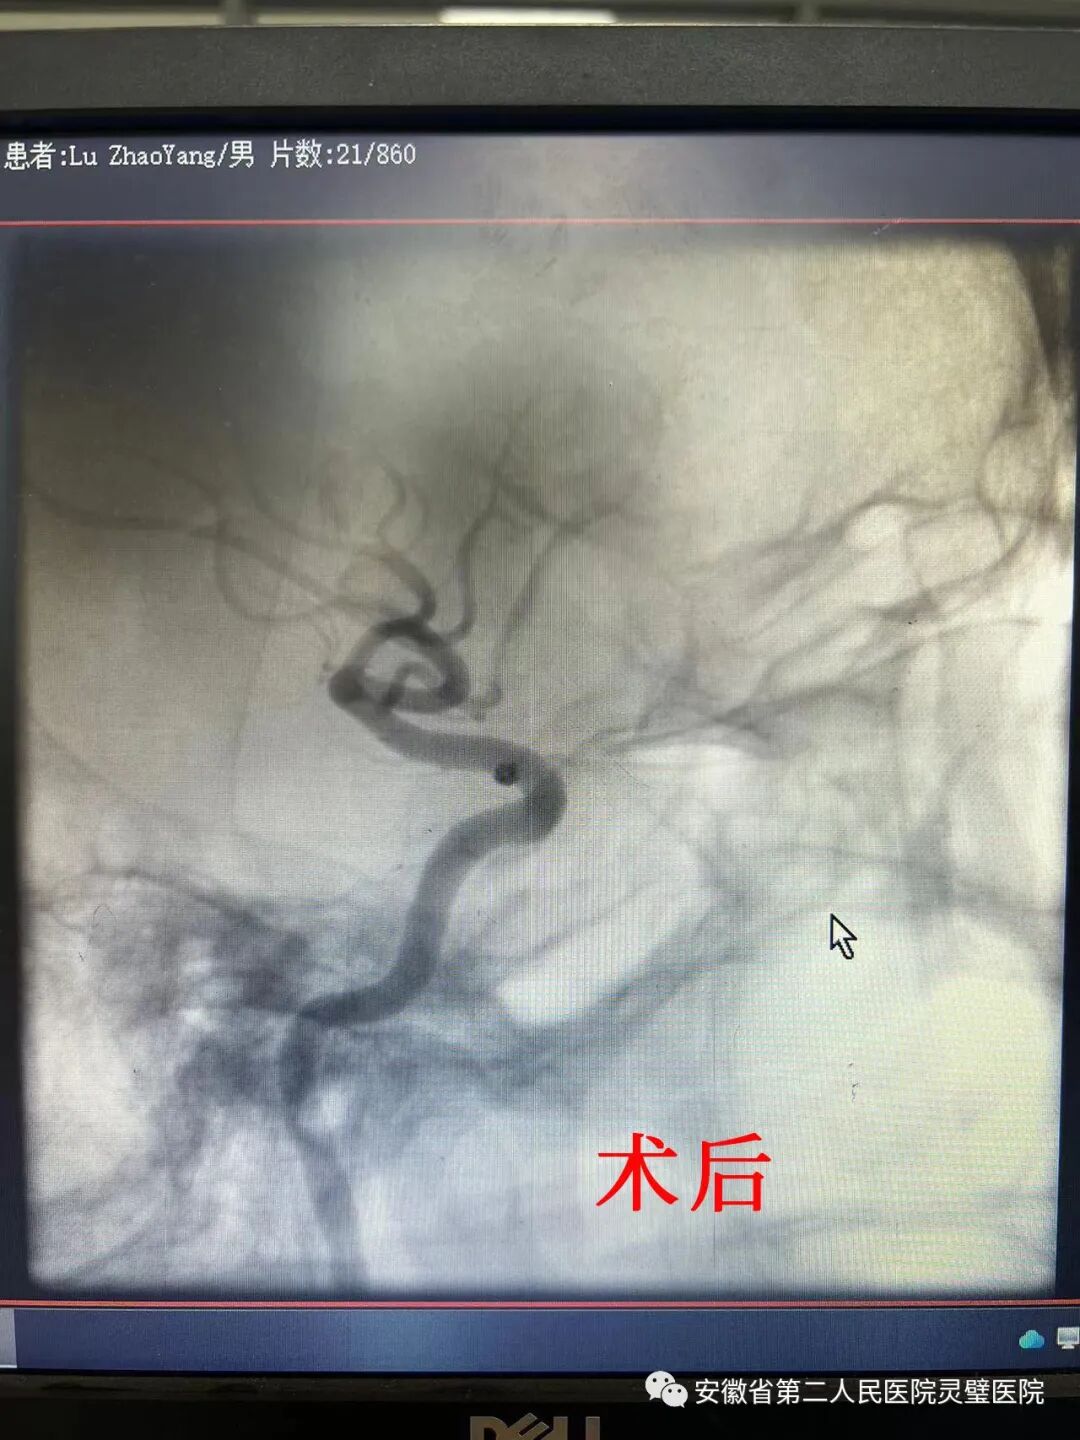

近日,32岁小伙突发意识障碍,出现无明显诱因下昏迷不醒,至我院就诊,发现竟是颈内动脉C6段动脉瘤作祟。神经外科急诊进行全麻下DSA全脑血管造影术+颅内动脉瘤血管内栓塞术,小伙顺利康复。

当日患者家属代诉,患者约2小时前无明显诱因下出现昏迷不醒,持续10分钟左右,无恶心呕吐,无四肢抽搐,未予任何治疗。至我院门诊行头CT检查示:蛛网膜下出血,头颅CTA提示左侧颈内动脉C6段动脉瘤,这宛如埋藏在患者体内的一枚“炸弹”,随时可能爆炸出血,死亡率极高。神经外科专家们立刻开展术前讨论,争取尽快治疗,挽救年轻生命。在介入科、麻醉科的专家全力配合下,经过迅速而完备的术前准备,神经外科在全麻下行全脑血管造影术+颅内动脉瘤血管内栓塞术。术中发现患者宽颈动脉瘤,弹簧圈单纯填塞难度较大,在支架辅助下,完美填塞,术后动脉瘤无血流,患者现恢复情况良好。